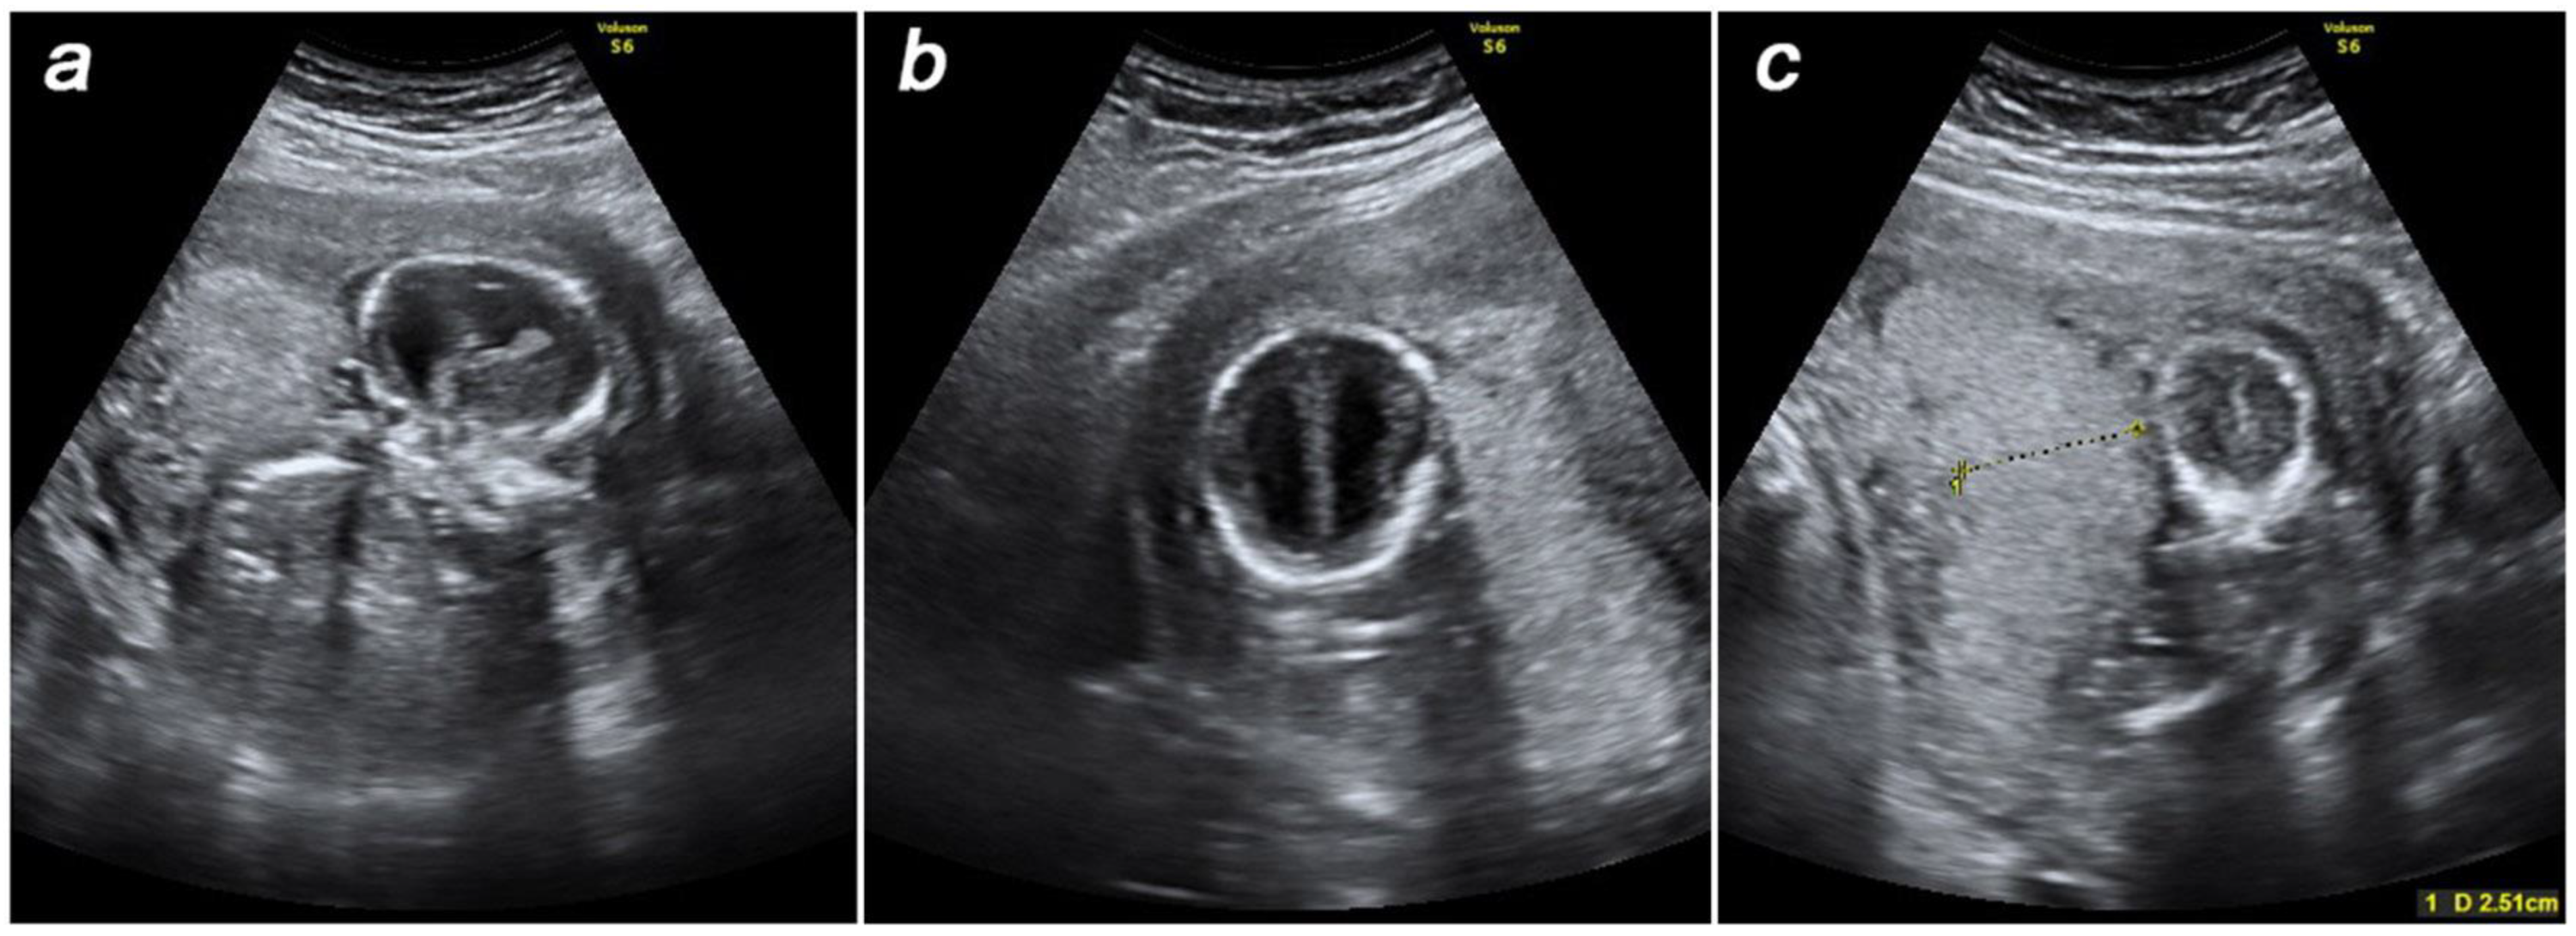

2. Detailed Case Description